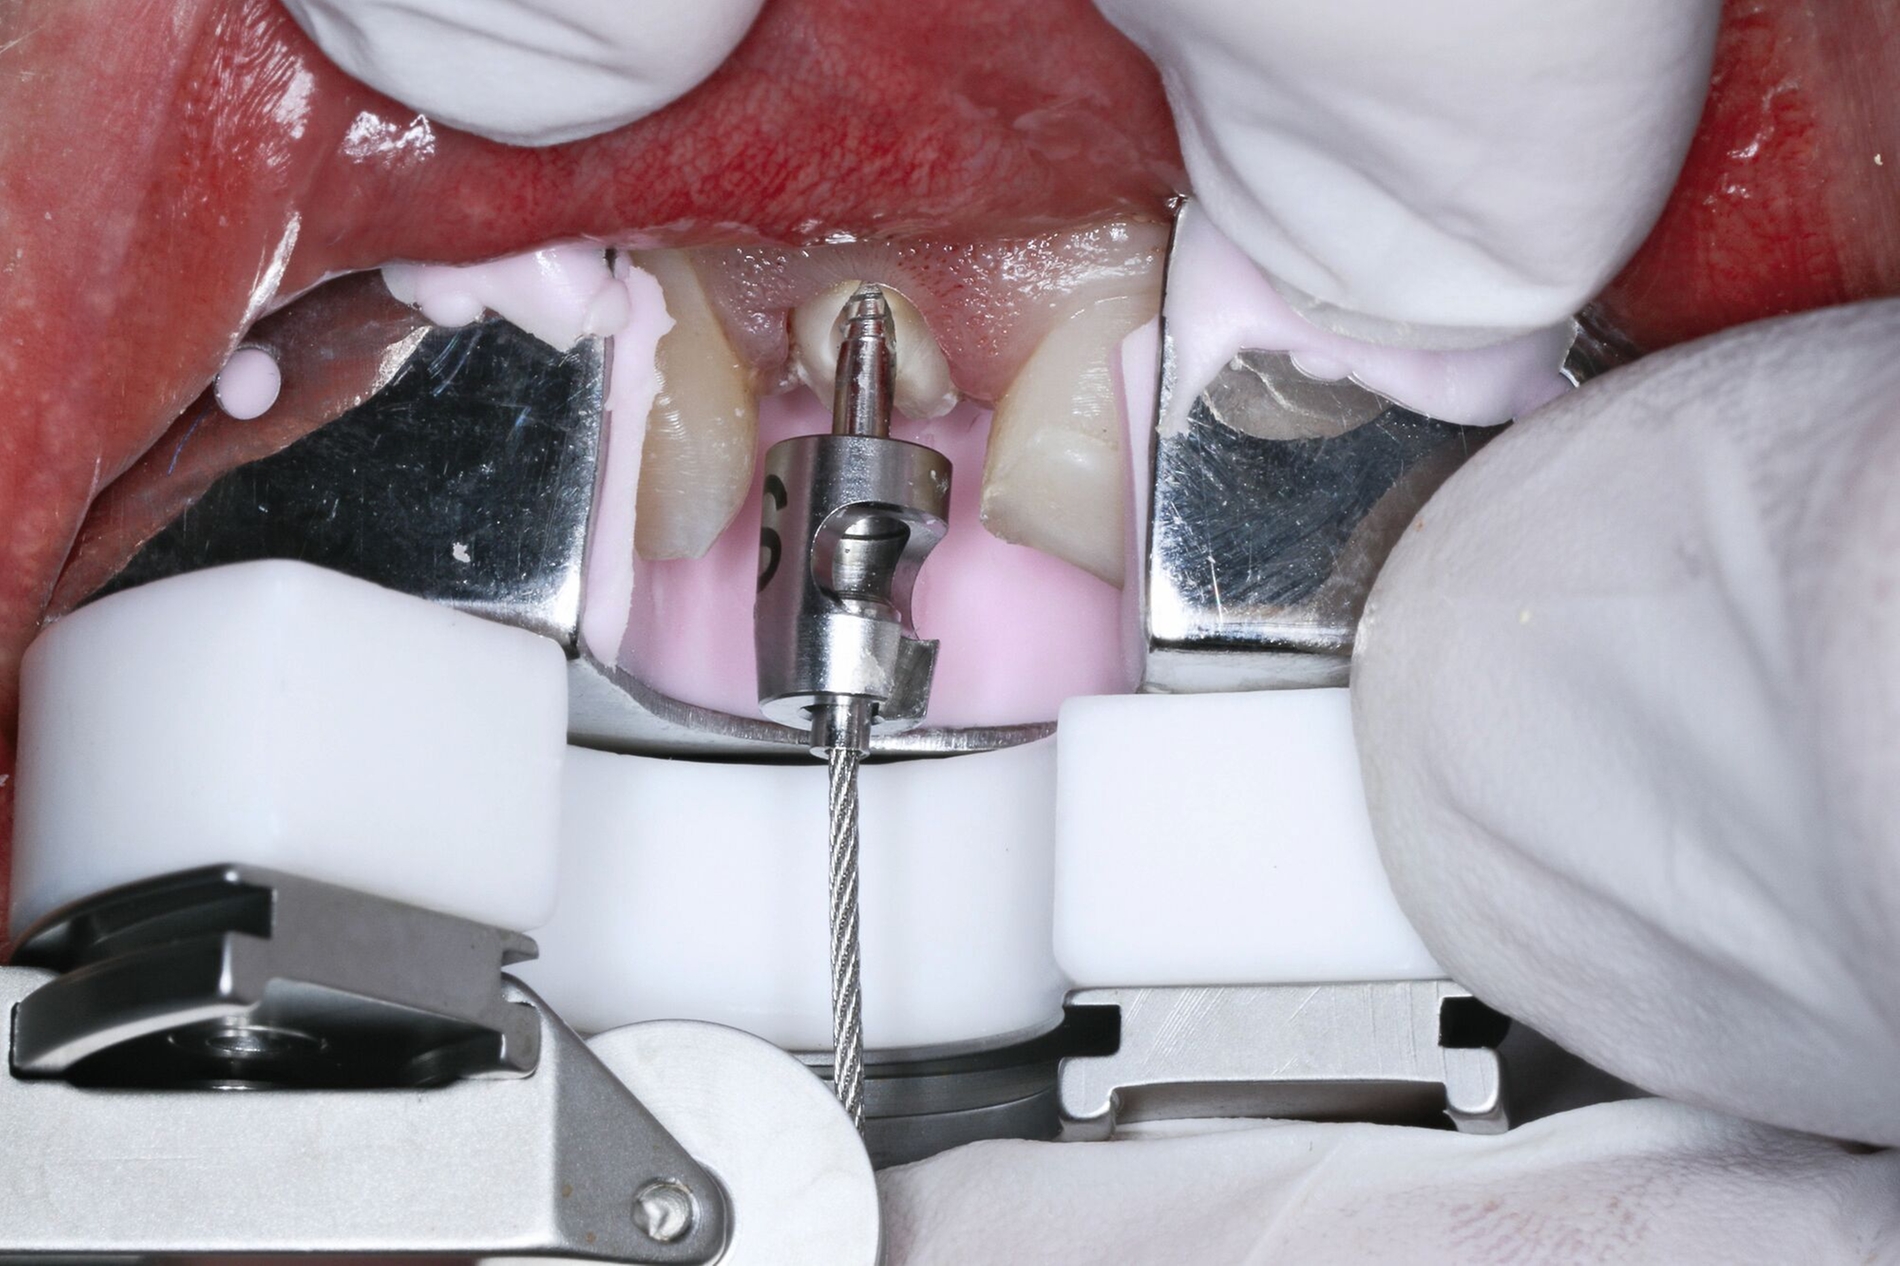

Nach einem vollständigen Zahnverlust oder auch nach einer erfolgten Dekoronation ankylosierter Zähne bietet sich insbesondere bei jungen Patienten die Versorgung mit einer Adhäsivbrücke an. Die einflügelige Adhäsivbrücke stellt eine minimalinvasive Möglichkeit zur Versorgung der Lücke bei Schneidezähnen dar (Abbildung 3). Für diese Versorgungsform liegen sehr gute Langzeitüberlebensraten von über 98 Prozent vor [Kern et al., 2017]. Einflügelige Adhäsivbrücken haben im Vergleich zu zweiflügeligen Adhäsivbrücken eine signifikant höhere Überlebensrate [Thoma et al., 2017].